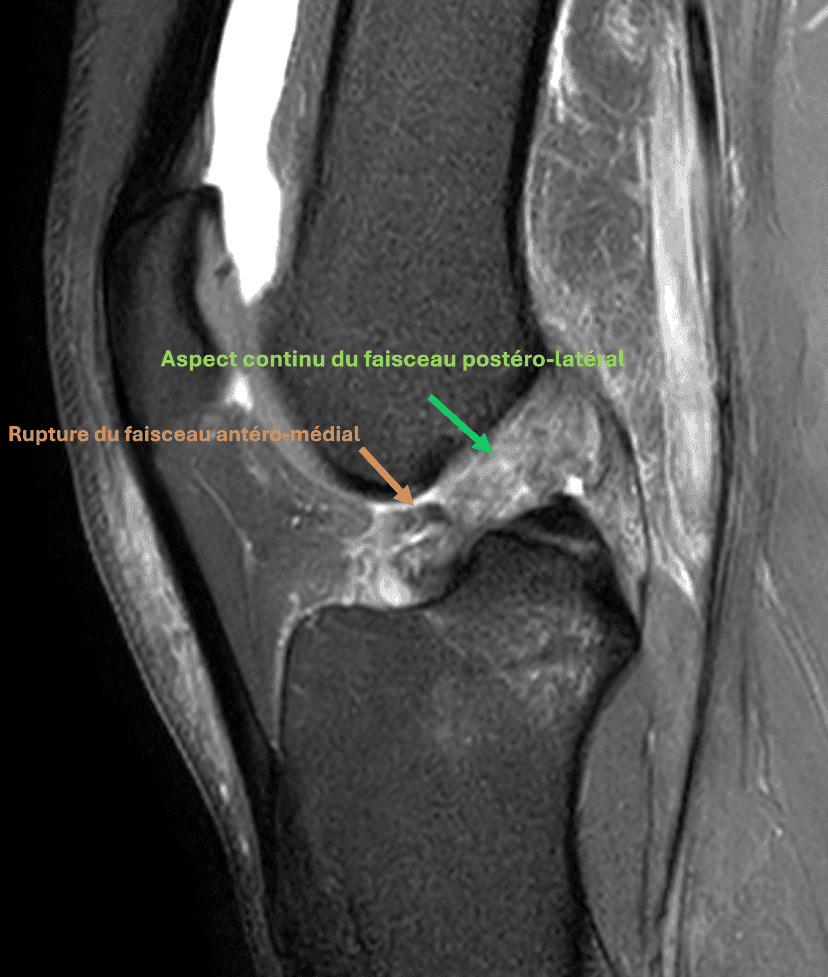

Rupture partielle du ligament croisé antérieur chez un sportif de 29 ans.

La rupture concerne le faisceau antéro-médial qui apparaît basculé en avant (flèche orange).

Le faisceau postéro-latéral apparaît continu (flèches vertes).